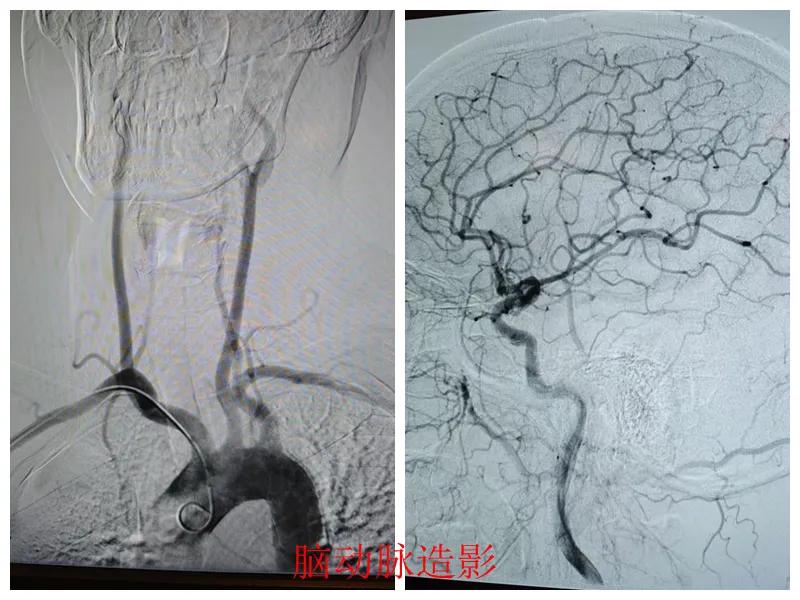

心腦聯(lián)防 腦心同治——市二院開展常態(tài)化心腦聯(lián)合造影

近日,市二院心血管內(nèi)科聯(lián)合介入科為患者成功實(shí)施了“心腦同治”聯(lián)合造影手術(shù),標(biāo)志著醫(yī)院在“心腦同治”介入治療方面取得了顯著進(jìn)展,為同時合并心腦血管疾病的患者查清了病癥,取得了良好的診療效果。

患者張某,47歲,因胸悶、左上肢麻木20天到市二院心血管內(nèi)科就診,結(jié)合既往冠脈CTA、頭頸聯(lián)合CTA結(jié)果、高血壓病史以及入院后的輔助檢查結(jié)果,診斷為冠狀動脈重度狹窄、頸動脈狹窄。

經(jīng)王瑾院長和心血管內(nèi)科、介入科多學(xué)科專家會診后,決定為患者進(jìn)行冠狀動脈和腦血管聯(lián)合造影檢查,一次性完成心腦血管評估,并同步開展腦血管及冠心病介入治療。

術(shù)前準(zhǔn)備完善后,在王瑾院長帶領(lǐng)下,心血管內(nèi)科主任李慧新、影像科主任宋貴良、副主任醫(yī)師趙進(jìn)科等緊密協(xié)作,成功為患者實(shí)施了冠狀動脈造影及腦動脈造影兩項(xiàng)檢查。冠狀動脈造影結(jié)果提示:患者右冠狀動脈慢性閉塞,腦動脈造影提示腦血管多支狹窄病變。

術(shù)后,根據(jù)造影檢查結(jié)果,科室團(tuán)隊(duì)為患者制定了個體化的治療方案,經(jīng)過一段時間的規(guī)范化治療,患者很快便康復(fù)出院。